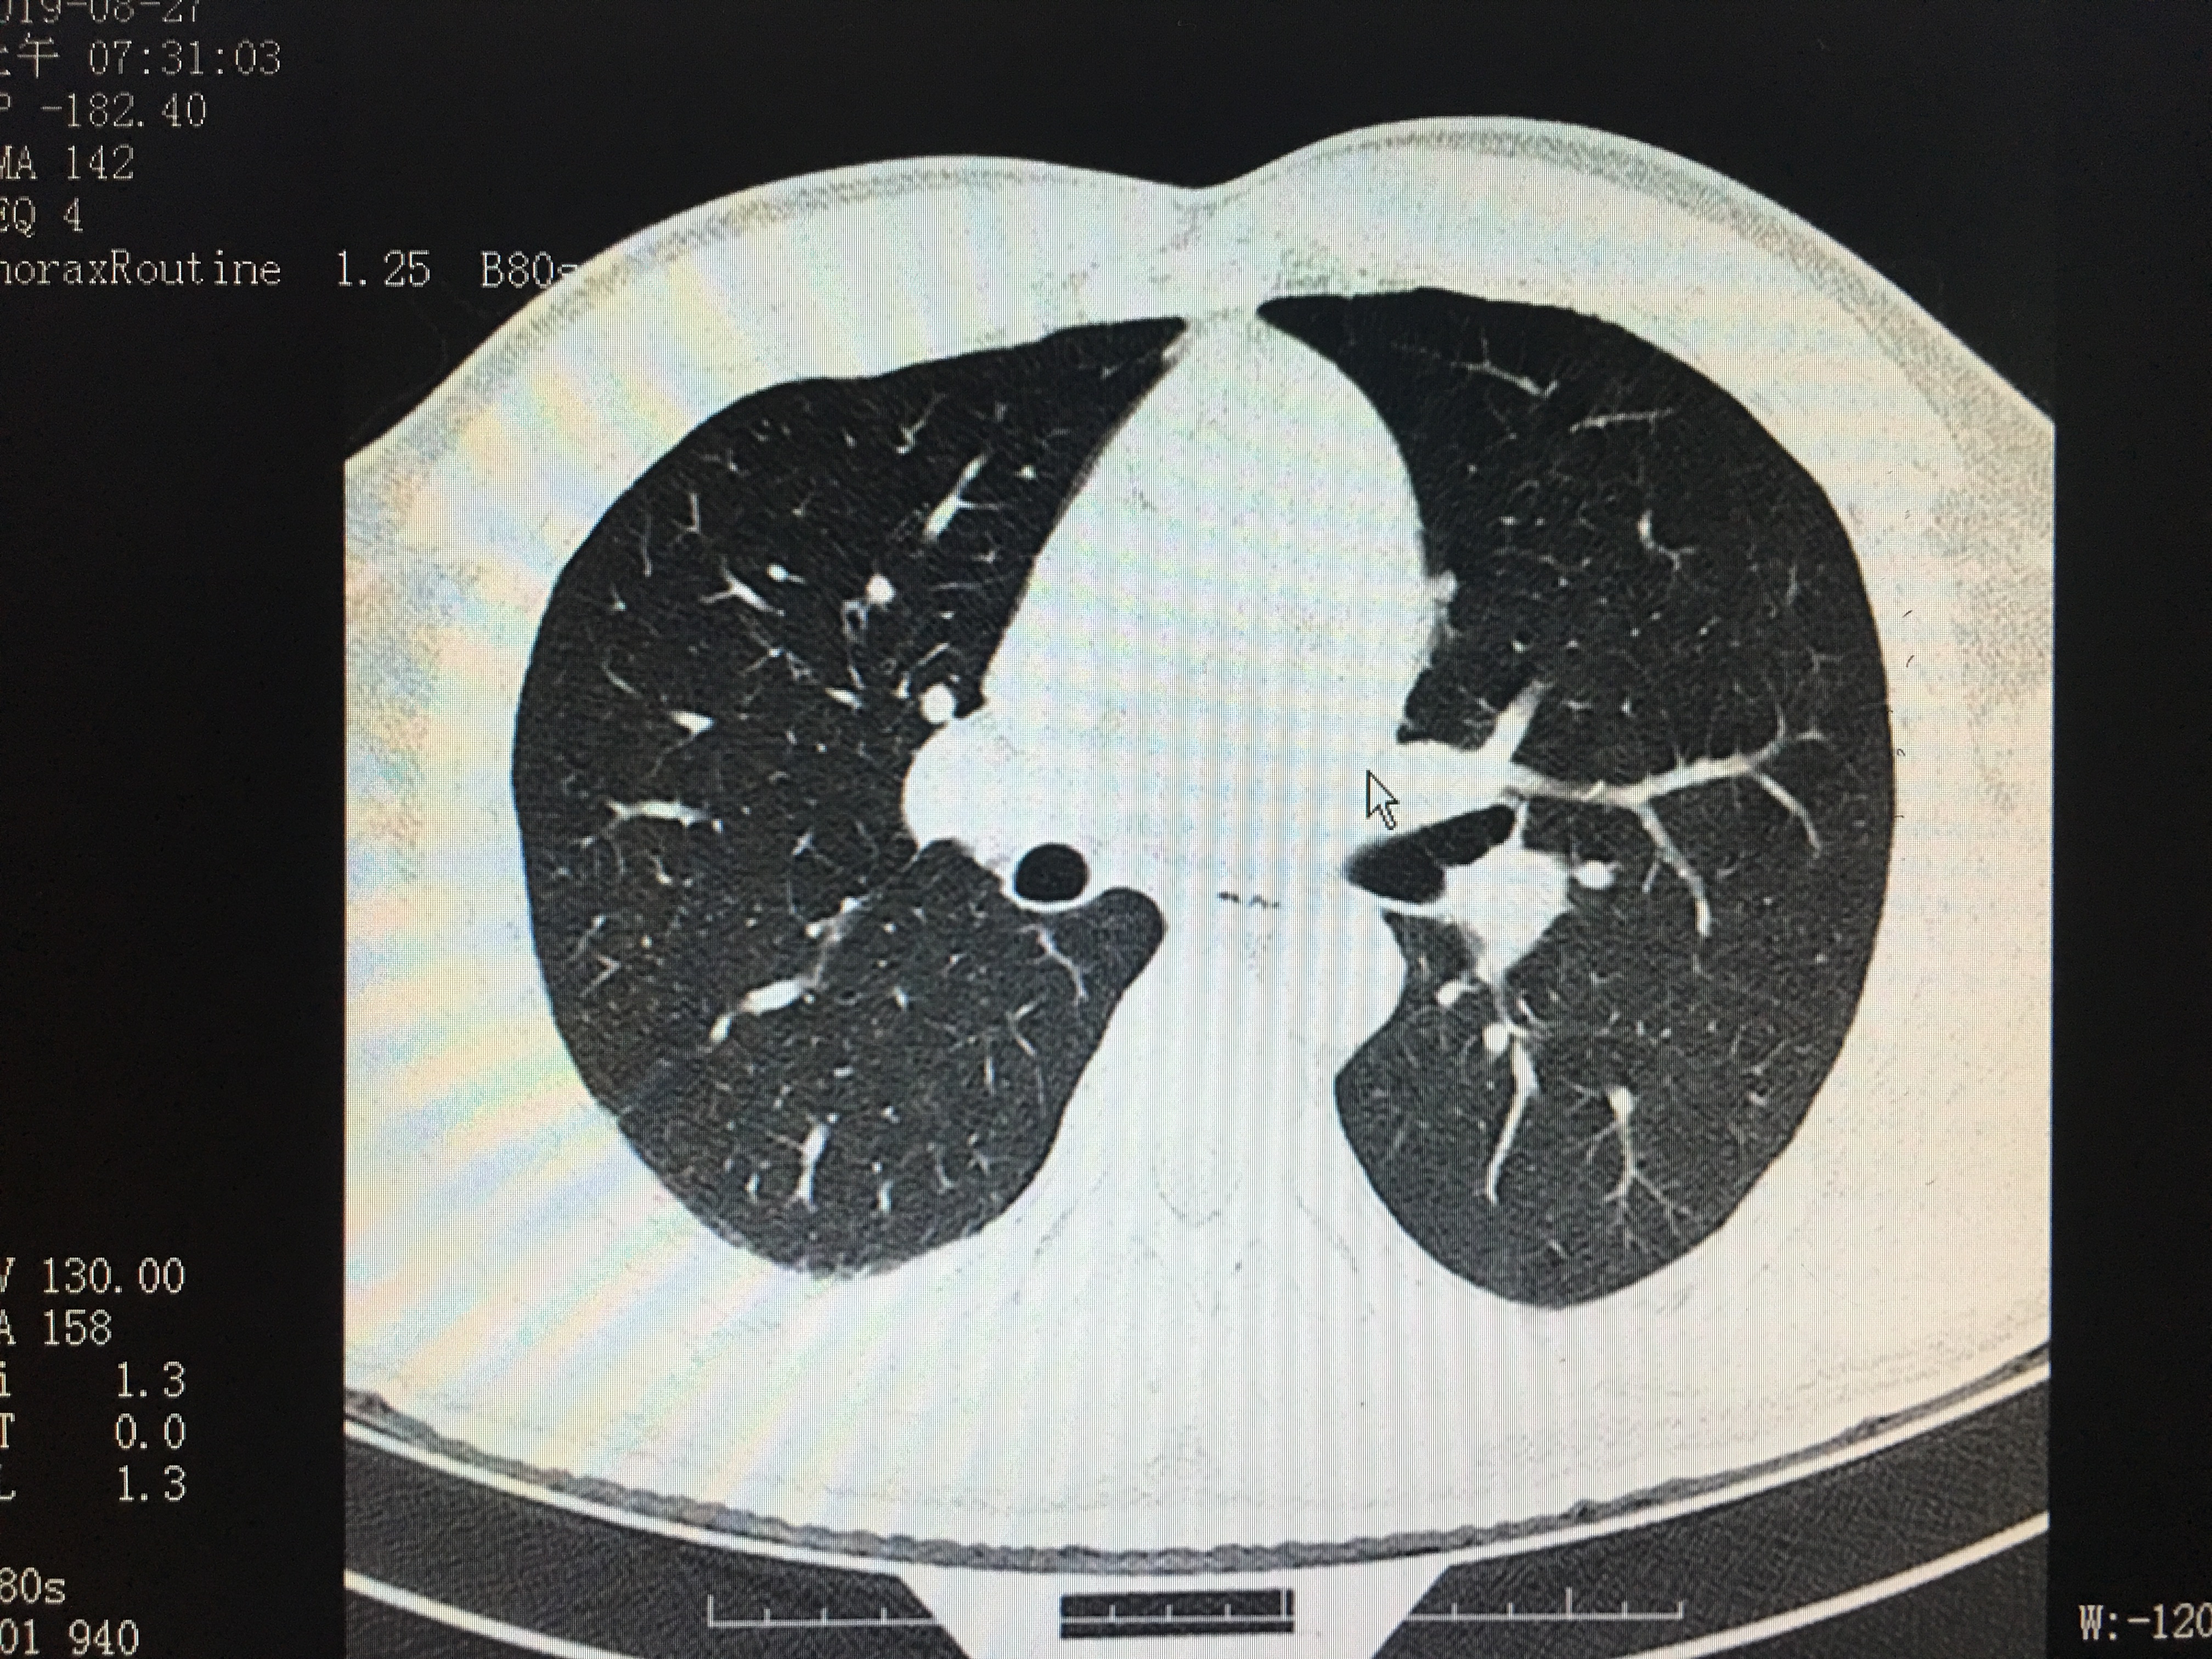

胸部CT是要求屏气做的

大家可以看一下下面两张图:

正常的胸部CT成像

相信这两个图像的区别很多人都能明显的看出来,第一张图明显比第二张清晰:图2显示模糊,伪影较多,就好像手机拍照时手抖了一样,而图一清晰更容易看出是否有病变存在。如图中,图一可明显看清双肺存在散在的结节灶,而第二张图因为没屏住气,形成的伪影比较多,就算有结节灶也未必能看出来。而肺部的结节灶大部分为良性的,一般建议定期复查,部分恶性病灶进展时通过复查对比可发现。

因为采集CT图像时,是射线一瞬间穿透人体投影成像的,人的胸廓因为呼吸活动起伏,很容易影响到成像时的信息采集。所以。做过胸部CT的人不知道有没有留意到:当影像医生将要采集CT图像时,会语音提示:“吸口气-屏住呼吸-可以呼气了”。所以这一小小提示,如果做好了,能更好的让专科医生能更清晰的看到你的检查结果,有助于判断的病情,使你的检查更加有价值哦。